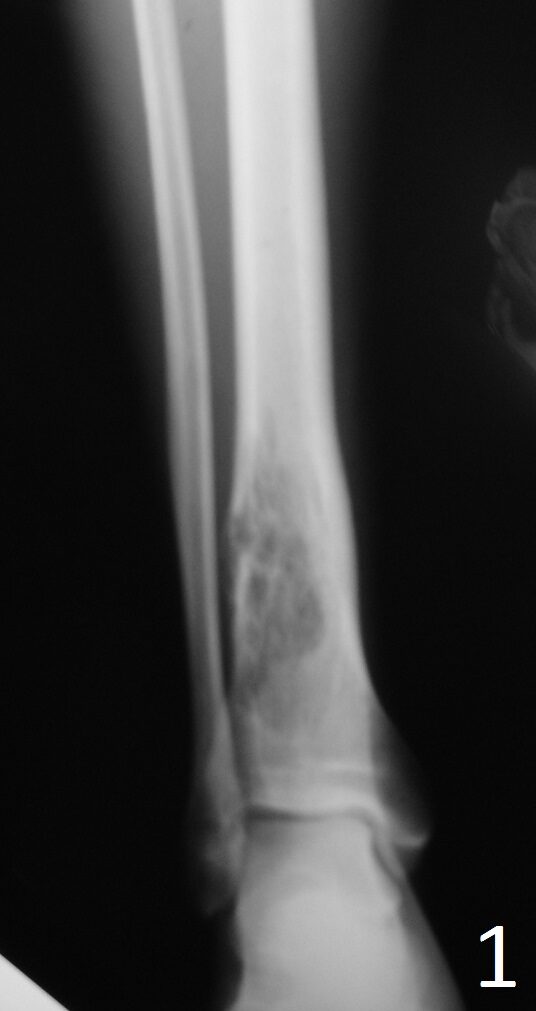

Plain x-ray (Fig. 1-2)

• Well-defined, lucent and expansile

• Possible cortical degradation

• Possible involvement of soft tissue

• More destructive, aggressive growth

• Shown by less-defined borders

• Pathologic fracture may occur

• Described as moth eaten

Fig. 1: AP and Lat (Fig. 2) Xray of tibia-fibula show a lucent distal tibia lytic lesion. Desmoplastic fibroma of bone often has thickened internal trabeculations and arises within the ceter of medullary canal.